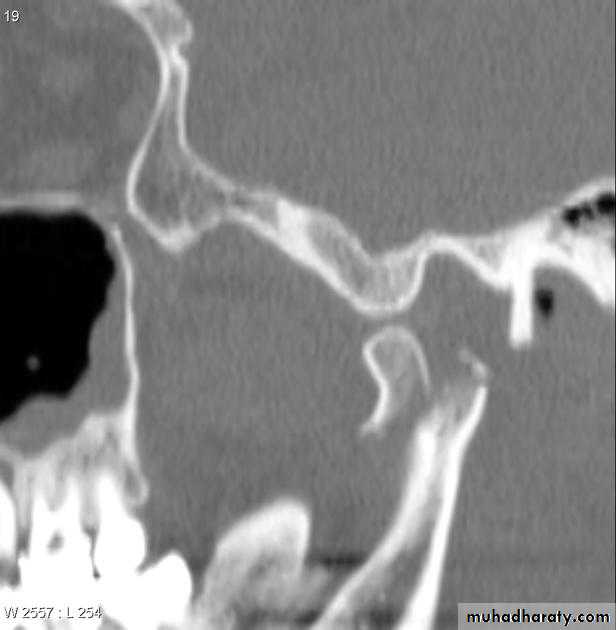

2. Extra-oral radiographsI. Oblique lateral of mandible (right and left side views); to evaluate thefracture line in the body, angle and condylar neck fracture.II. Postero-anterior view of mandible; to evaluate body and angle #together with the type of displacement.III. Panoramic tomogram, or orthopantomogram (OPT): the best single overallview of the mandible, including excellent view of the condyles.tic resonance imaging); which gives very accurate details.

IV. Reverse Towne's view (elongated PA); to demonstrate fractures of thecondylar neck.v. Temporomandibular joint views (in open and close mouth); todemonstrate the presence of TM dislocation (Transcranial,Transpharyngeal, Arthrography, and Arthroscopy)VI. CT scan (computerized tomography scanning); to evaluate intracapsular fracture of the condylar head.VII. MRI